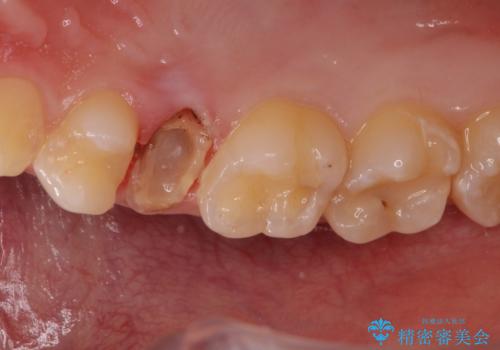

歯を引っ張り出したり、歯肉の手術の経過待ちの間に、患者様のご希望で他の歯の虫歯治療も行いました。

・十分に引っ張り出した後、歯肉の手術が必要となります。

・歯肉が落ち着いてから最終的な被せものの製作となります(約3か月)。